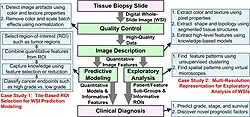

Imaging informatics in pathology as a whole allows for a wide range of disease detection and analysis. The most prominent use in pathology is with the detection and analysis of different forms of cancer. Diagnosing cancer manually is a pain staking and subjective process which includes examining what could be millions of cells. Through various clinical decision support systems(CDSS), professionals can ease the manual labor of tissue region selection, using Whole-Slide Imaging(WSI) tools to maximize the information analyzed. Several predictive models aimed to identify regions of interest within WSI, requiring training before use. Unsupervised models are being introduced, but are currently less prominent. An example of an unsupervised model being used is detecting tissue folds by using an unsupervised method to cluster the pixels in an image representing the difference between saturation and intensity values for every pixel. Due to being an unsupervised model, this method has some limitations. These limitations being that it has low sensitivity for different types of tissue folds within an image, and it has low specificity for images without tissue folds.[20]